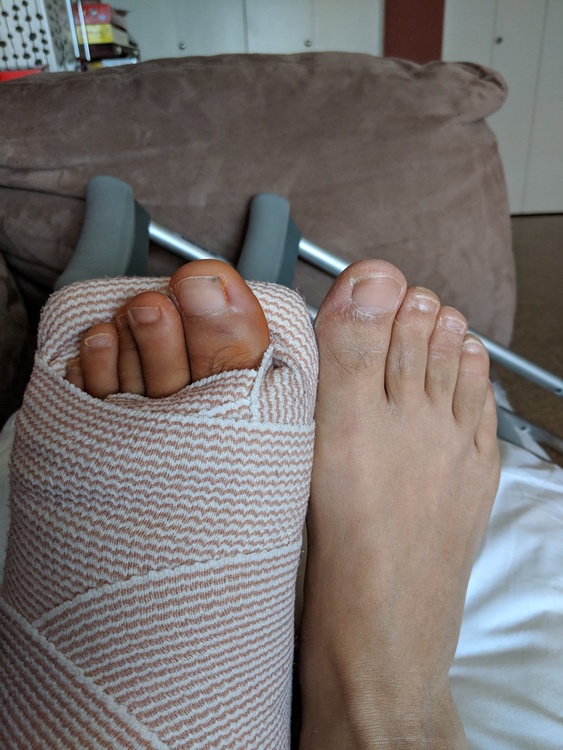

Good to hear ech day is better Pete. The swelling takes time to come down. Mine took a couple of months. Did your doc confirm no foot pressure for 3 months? |

Hi Steve, hope u getting better and you're progressing, now , I'm off pain meds no more hydrocodone.,only one aspirin a day and vitamin D and calcium,,now u suggested to wiggle my toes on leg but how? with my hand or trying using the leg nerves? Since most of it is in cast..im trying to massage ,give little touch with my hand to the leg as much I can but most of it is in cast....next Friday I'll go doc after surgery fallow up and will ask allot questions about this ,after all I got charged an arm and a leg for this surgery,,literally.... |